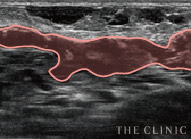

実際のエコー画像

-

施術前

アクアフィリング豊胸のしこりが散在し、一部は塊に -

溶解中

エコー下でしこりにアプローチし、確実に生理食塩水を注入 -

除去したアクアフィリング

完全に溶解しないケースでも、エコー下できれいに吸引除去